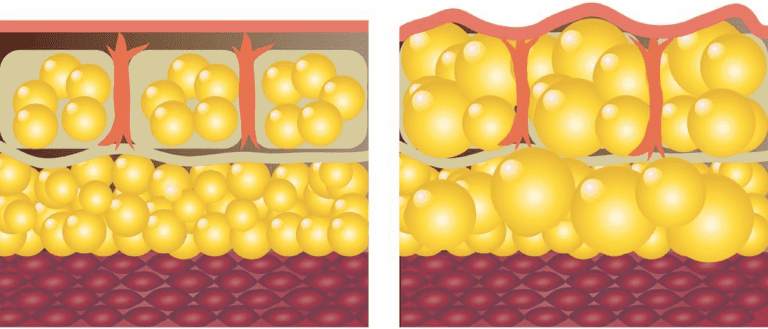

Das Lipödem ist nach der Definition der S1 Leitlinie AWMF eine chronisch progrediente Erkrankung, die nahezu ausschließlich bei Frauen auftritt und durch eine Fettverteilungsstörung mit deutlicher Disproportion zwischen Stamm und Extremitäten gekennzeichnet ist.

Diese entstehen aufgrund einer umschriebenen, symmetrisch lokalisierten Unterhautfettgewebsvermehrung. Zusätzlich bestehen Ödeme, die durch Orthostase verstärkt werden, sowie eine Hämatomneigung nach Bagatelltraumen. Charakteristisch ist eine gesteigerte Druckschmerzhaftigkeit, meist bestehen Spontanschmerzen. Die Ursache des Lipödems ist bisher unbekannt. Eine genetische Komponente wird aufgrund von positiven Familienanamnesen angenommen. Die erkrankten Fettzellen lassen sich nicht durch Sport oder Ernährungsmaßnahmen beeinflussen. Eine fehlende Transportfähigkeit der Lymphgefäße führt sekundär zu einem Stau an lipid-und proteinreichen Substanzen rund um die Adipozyten. Da der Abtransport nicht gewährleistet ist, kommt es zu einer vermehrten Ansammlung ebenfalls in den Adipozyten. Sekundär entwickeln sich in höheren Stadien ein chronisches Lymphödem und eine Fibrosierung der Adipozyten. Die charakteristische Fettverteilungsstörung der erkrankten Adipozyten lassen sich an den Extremitäten erkennen durch das Aussparen von Händen und Füßen, sowie einem typischen „Säulenbein“ und verstrichenen Konturen. Kennzeichnend für ein Lipödem ist außerdem die Gefäßfragilität, die sich durch ein leichtes Auftreten von Hämatomen bei inadäquatem Druck oder Berührung der Extremitäten ergeben. Des Weiteren klagen die Patientinnen meist über Ruheschmerzen in den Beinen, vor allem nach längerer Belastung. Die konservative Therapie mittels Kompressionstherapie und manueller Lymphdrainage beschränkt sich auf die symptomatische Linderung.

Die einzige nachgewiesene Therapie des Lipödems ist die radikale zirkuläre Liposuktion, die mit überdurchschnittlich hohen Kosten einhergeht und von den Krankenkassen in der Regel nicht übernommen wird. Diese Form der Therapie zeigte in Langzeitstudien eine Wiederherstellung einer hohen Lebensqualität und kaum Rückfallquoten. Aktuell gibt es eine unklare Studienlage zur Pathogenese des Lipödems und kaum Forschung zur molekularen Ätiopathogenese. Ziel dieser Studie ist es daher, die molekularbiologische Pathogenese dieses Krankheitsbildes zu erforschen und die Adipozyten in vitro Kultur auf unterschiedliche Faktoren zu untersuchen. Alle für die Studie ausgewählten Patientinnen leiden an Lipödem vom Ganzbeintyp (nach Herpertz) im Stadium II Grad II (nach Fife, Meier-Vollrath). Die Vergleichsgruppe wird von Patientinnen ohne diagnostiziertes Lipödem gebildet, deren Fettzellen durch die gleiche Liposuktionsmethode gewonnen werden.

Die Studie wird in Kooperation mit der Praxis Dr. Dominik von Lukowicz durchgeführt, der sich als Facharzt für Plastischen und Ästhetische Chirurgie auf die Behandlung des Lipödems spezialisiert hat und über jahrelange Erfahrung im Bereich der speziellen Liposuktion bei Lipödem verfügt.

normales Fettgewebe I Lipödem-Fettgewebe